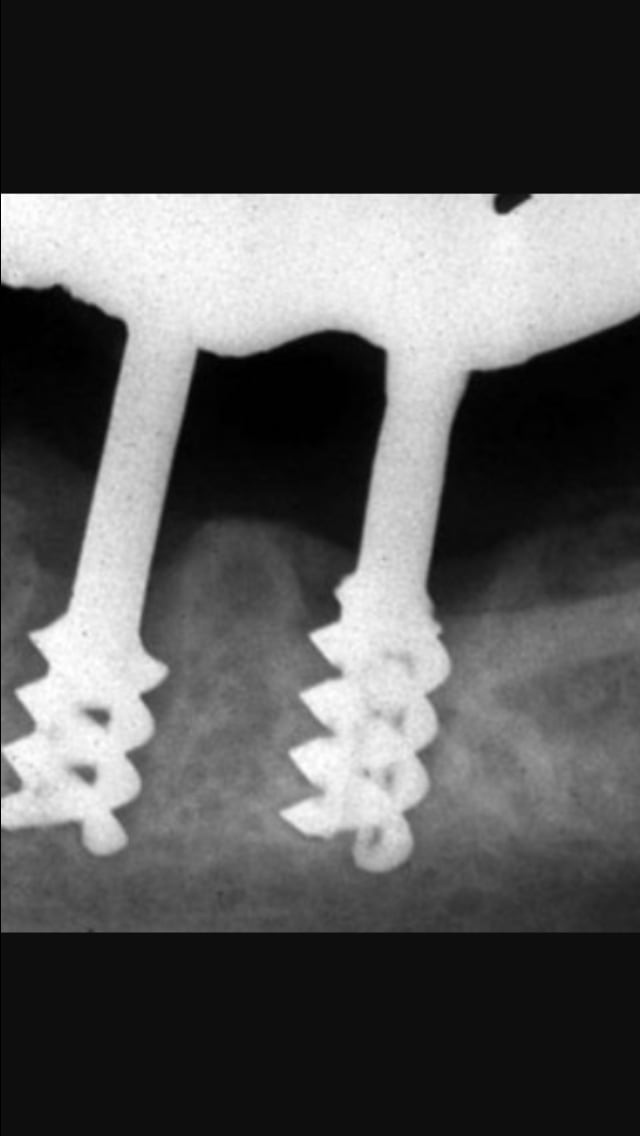

- implants spirales ou Implant chercheve

- Implant vis creux avec events

- Et je suis tombé aussi sur un Frialit sans spires. Un frialit impacté donc ?!